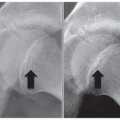

Osteochondritis dissecans (OCD) of the capitellum is a common cause of pain and functional limitations in adolescent upper extremity weight-bearing or overhead athletes

Patients present with pain, loss of elbow motion, and mechanical symptoms of locking or giving way

Radiographs and advanced imaging—particularly magnetic resonance imaging (MRI)—will confirm the diagnosis and aid in classification